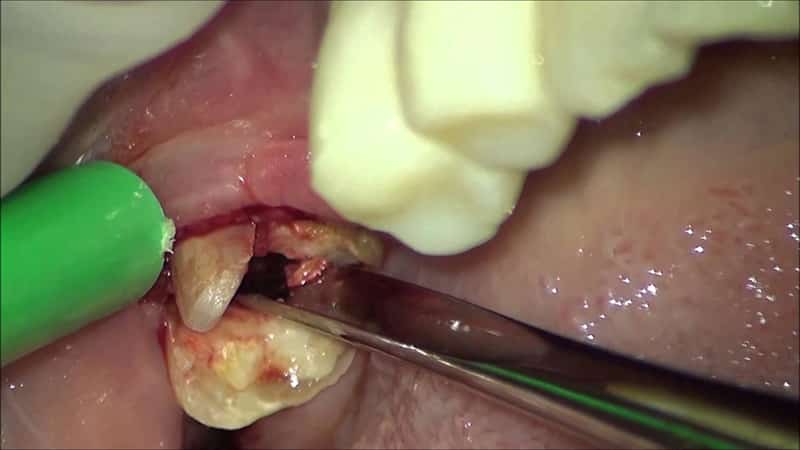

В таких ситуациях удаление зуба мудрости на верхней челюсти, примеры которого можно увидеть в галерее статьи, осуществляется с помощью байонетных щипцов. Этот инструмент имеет особую конструкцию, так как даже при отсутствии видимых осложнений извлечь восьмерку может быть непросто. Если зуб сильно разрушен, заостренные и полностью смыкающиеся концы щипцов обеспечивают надежную фиксацию для врача.

Перед удалением моляра стоматолог, как правило, назначает рентгенографию челюсти, чтобы оценить объем предстоящей работы и выбрать наилучшую стратегию. Это поможет избежать возможных осложнений, повреждения соседних зубов и мягких тканей десен как во время процедуры, так и после нее.

Затем врач собирает анамнез, опрашивая пациента о наличии различных заболеваний, чтобы определить необходимость хирургического вмешательства и правильно выбрать анестетик. С зуба мудрости удаляют налет и проводят антисептическую обработку десен, чтобы предотвратить послеоперационное гноение раны.

После выбора инструмента стоматолог вводит пациенту местную анестезию. Процесс удаления проходит в следующей последовательности:

- аппликация и фиксация инструмента в оптимальных точках для тракции;

- раскачивание моляра;

- извлечение восьмерки из губчатого тела альвеолы (тракция);

- остановка кровотечения и формирование кровяного сгустка в ране.